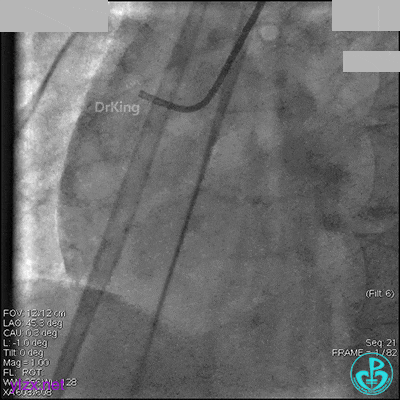

先处理前降支开口严重狭窄并顺利植入前降支到左主干支架。

没有说明是否进行了右冠脉介入治疗。